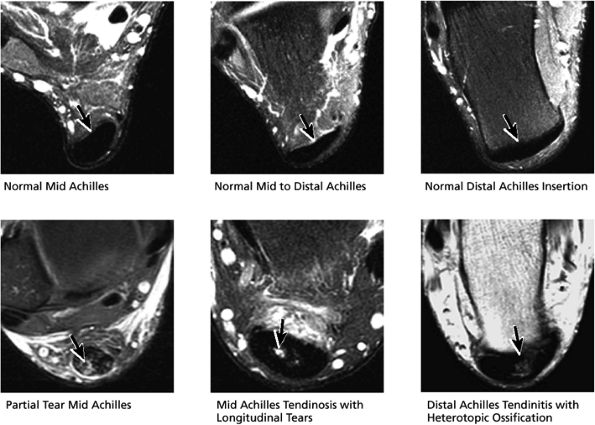

FIGURE 5.53 Posterior Tendons.